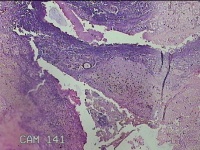

宫颈6点、10点、12点组织

性别

女

年龄

30岁

临床诊断

女性盆腔炎;宫颈炎性疾病;异常子宫出血

一般病史

宫颈HPV-56(+),TCT见非典型鳞状上皮细胞

标本名称

大体所见

1.“宫颈6点组织”:灰白暗红色不规则组织0.5x0.3x0.2cm一块。 2.“宫颈10点组织”:灰白暗红色不规则组织0.3x0.2x0.1cm一块。 3.“宫颈12点组织”:灰白暗红色不规则组织0.8x0.5x0.3cm两块。

图4

CIN1